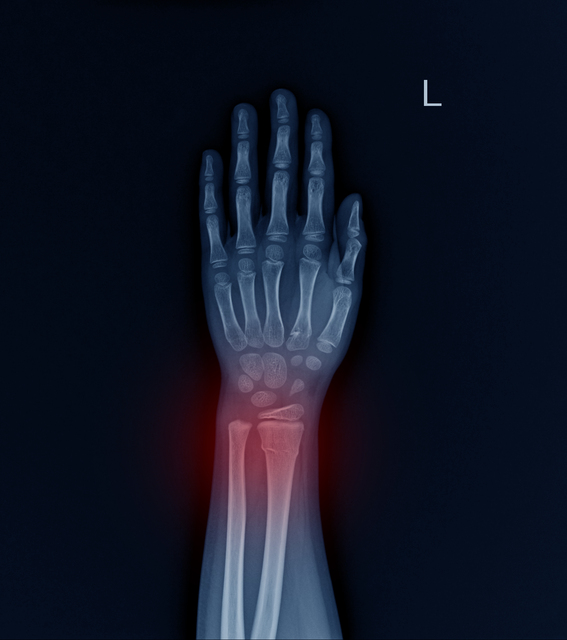

특히 주목할 점은, 고관절 골절의 약 95%가 낙상으로 인해 발생한다는 것입니다. 낙상과 같은 작은 충격으로 인한 골절을 저에너지 골절(low energy fracture)이라고 부릅니다.

저에너지 골절이란 일반적으로는 골절이 일어나지 않을 정도의 약한 충격, 예를 들어 의자에서 일어나다 넘어지거나 가벼운 낙상으로도 뼈가 부러지는 현상을 말합니다. 골다공증 환자는 이런 작은 사고로도 쉽게 골절이 발생할 수 있어, 일상생활 중 항상 위험에 노출되어 있습니다.